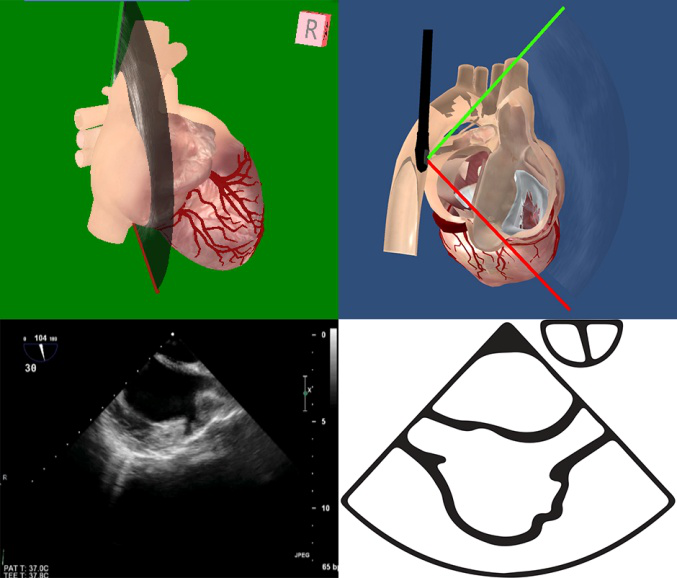

TEE切面可用来评估二尖瓣系统的每一部分,检查时将探头送至食管中段,操纵探头调整成像的角度使声平面对准二尖瓣环中心,探头晶片置于0~10度食管中段4腔心切面后开始旋转声平面,依次获得食管中段二尖瓣交界切面、食管中段左心室2腔切面、食管中段左心室长轴切面,在各个标准切面上可以观察不同小叶的功能状态,各个小叶与标准切面的对应关系如下图所示。

图10 TEE评价二尖瓣形态和功能的基本切面(标注二尖瓣分区)

TEE切面与二尖瓣分区的对应关系可用于二尖瓣脱垂部位的判断,但要注意的是:一定要将2D或3D图像与二尖瓣模型对应起来,不理解切面和模型之间的空间关系,直接用文献上的分区对应实际的超声图像会导致定位不准和交流障碍(图11,12,13,14);另外,经胃底基底段短轴切面对诊断瓣叶裂和穿孔很有帮助,彩色多普勒可以提供有关反流束起源的信息(图14)。

图13食管中段左室长轴切面显示二尖瓣后叶P2区腱索断裂并脱垂

图14经胃底基底段短轴切面。示二尖瓣前后叶,P3区位于“扇形”的顶点